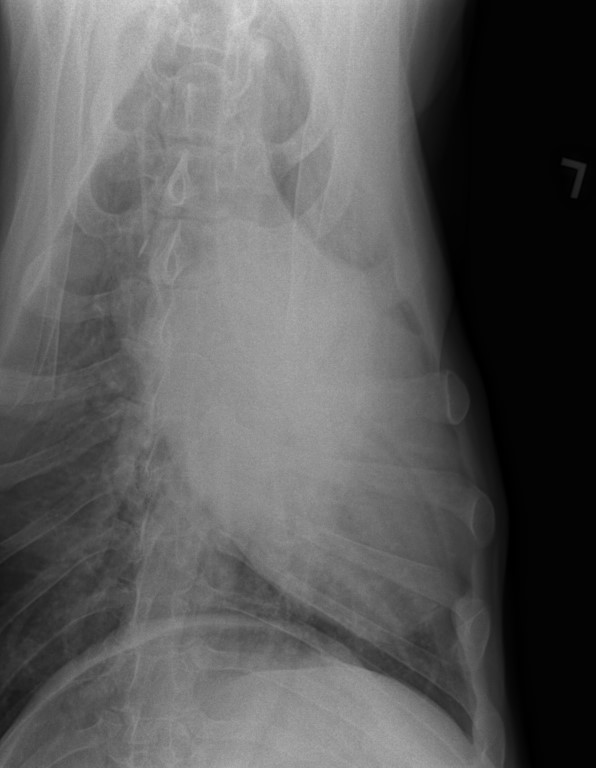

The Vet and I discussed x-days of her chest/lungs for her Vet was not comfortable with the looks of that remaining mass. frown emoticon Nor, with this sudden huge weight loss.

I was so worried gowning up to help with the x-Rays……

The good news is that her lungs, at this time have shown no signs of anything that has metastisized.

I have her x-Rays to post on her blog, photo’s of her masses and, one of a recovering sweet BHRR’s Ani from sedation. She also received a lovely mani/pedi!